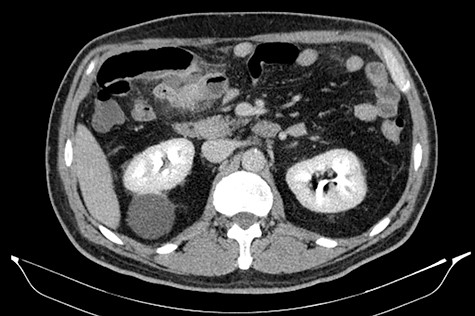

A 53-year-old man with a 10-day evolution of mild COVID-19 was admitted to the emergency department. He had a 2-day evolution, severe and sharp abdominal pain, which was located in the epigastrium, worsening in intensity on the last day. He also reported fever (38°C). The patient did not have nausea, vomit, abnormal bowel movements, other respiratory symptoms or urinary complaints. His medical history included arterial hypertension, dyslipidemia and a previous myocardial infarction submitted to coronary bypass surgery in 2013. A physical examination revealed a febrile (38.1°C) and stable patient (blood pressure (BP): 125/82 mmHg; hazard ratio (HR): 89 bpm). Cardiopulmonary auscultation was normal. His abdomen was non-distended, and tender mass in the epigastrium with localized guarding was noted. Bowel sounds were hypoactive and non-metallic. No abdominal hernias were identified. Laboratory exams revealed a normal white blood cell count (8.130/μl; segmented neutrophils, 72.9%), a hemoglobin level of 13.80 g/dl, a C-reactive protein level of 22.10 mg/dl, a d-dimer level of 0.94 μg/ml and normal hepatobiliopancreatic, cardiac and renal biochemical parameters. Urinalysis and the arterial-blood gas test were also normal. Ultrasonography was not performed due to its unavailability at the hospital on that day. A computed tomography (CT) scan with intravenous contrast of the abdomen was obtained, detecting a short segment of small bowel with inflammatory signs and localized free peritoneal fluid (Fig. 1). The pulmonary bases had residual ground-glass opacities related to COVID-19 (Fig. 2). Common diagnosis such as cholecystitis, pancreatitis or perforation of hollow viscus were ruled out. Given the lack of a preliminary diagnosis and the evidence of ongoing abdominal sepsis, the patient was proposed for a diagnostic and potentially therapeutic exploratory laparotomy. The intraoperative findings revealed a suppurative Meckel’s diverticulitis with local abscess, found at about 50 cm from the ileocecal valve (Fig. 3). Drainage and a segmental ileal resection with primary anastomosis were performed. In the postoperative period, inflammatory markers were responding positively to intravenous antibiotics and no further rises in temperature were observed. In addition, no complications were reported, and the patient was discharged on postoperative Day 6. The anatomopathological examination revealed small bowel with active inflammation and gangrenous Meckel’s diverticulum.

Short segment of small bowel with inflammatory signs and localized free peritoneal fluid (CT scan).